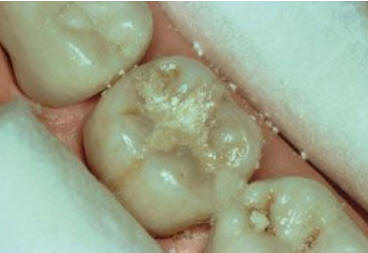

Una morfología de la fisura estrecha, con forma de botella de "Coca-Cola" genera un nicho ecológico ideal para la colonización de cualquier bacteria productora de ácidos. Al no poder remover en forma períodica dicho biofilm de una zona tan estrecha, el ataque ácido genera una lesión cariosa en la dentina, con un aspecto de esmalte intacto a la inspección visual, o sea un típico código 3 y 4 de ICDAS Completo. (Caries Moderada para el ICDAS COMBINADO)

Por este motivo es importante realizar el sellado de las fosas y fisuras de molares y premolares cuando comienza su erupción dentaria, como método de prevención eficaz de caries.

Imagen digital que representa la microfiltración y penetración del sellante realizado.

Microfotografía: Muestra como el sellador obtura la caries subyascente, evitando su avance.

Código 3 (Caries moderada) in vitro. Los códigos 3 in vivo debe ser sellado para evitar el avance del proceso carioso. (MNO)

Código 4 (Caries moderada) in vitro. Los códigos 4 in vivo deben ser tratados en forma operatoria con preservación dental (MOPD), porque presentan dentina infectada.